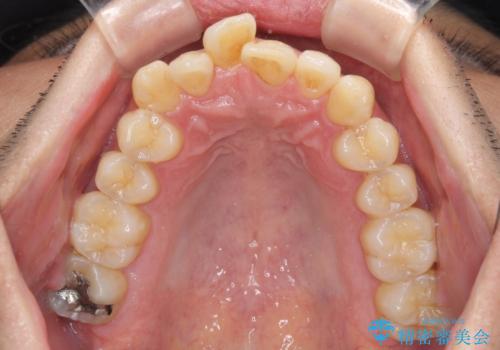

前歯のデコボコ ワイヤー装置での短期間治療

- 前歯のデコボコを気にして来院された患者様です。

インビザラインまたはワイヤー装置、どちらでも対応可能でしたが、自己管理の少なさ、期間の短さから、ワイヤー装置による矯正治療を行うこととしました。